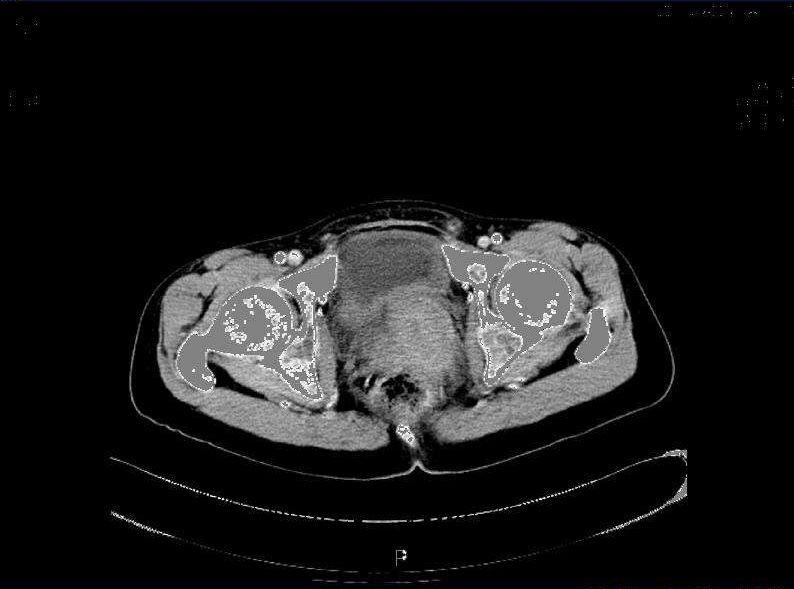

上腹部盆腔CT示: 1、胃体胃壁稍增厚,胃周可见小淋巴结,请结合临床。 2、盆腔巨大占位灶,转移瘤考虑。 3、腹盆腔少量积液。 4、胸腰椎及骨盆多发骨转移考虑。

图1  2017年5月26号CT影像